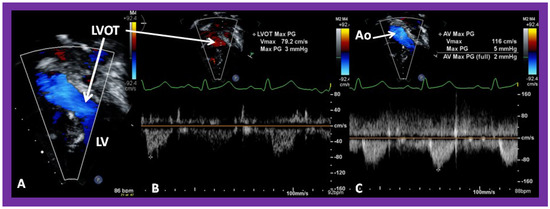

Figure 41. Selected video frames from an apical views demonstrating laminar flow from the left atrium (LA) to the left ventricle (LV) (A) and from the LV to aorta (Ao) (B). Note laminar flow in the LV outflow tract (LVOT) (B). Medial portion of the conduit (C) is seen in (A).

Applsci 11 09472 g041

Figure 42. Selected video frames from an apical view demonstrating laminar flow from the left ventricle into the aorta (Ao). Note laminar flow in the LV outflow tract (LVOT) and low Doppler flow velocity (~0.8 m/s).

Applsci 11 09472 g042